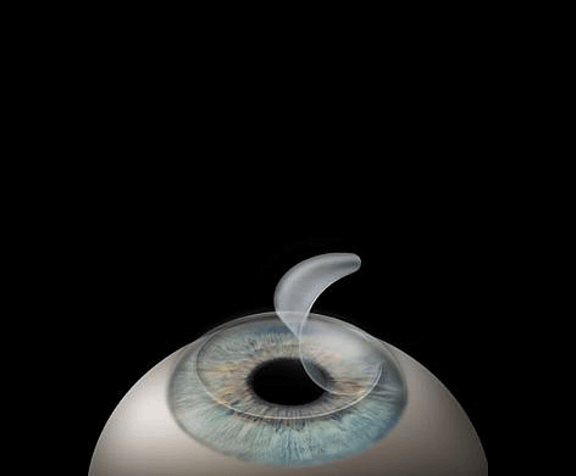

Cataract Surgery

MICS – Microincsiional Cataract Surgery. Phacoemulsification. SICS – small incissional cataract surgery. Secondary IOL. After cataract Laser with multifocals. Toric and Monofocal IOLs.

Refractive Services

Refractive surgeries, Refractive Multifocal lenses, ICL, LASIK, EPILASIK, Keratoconous.